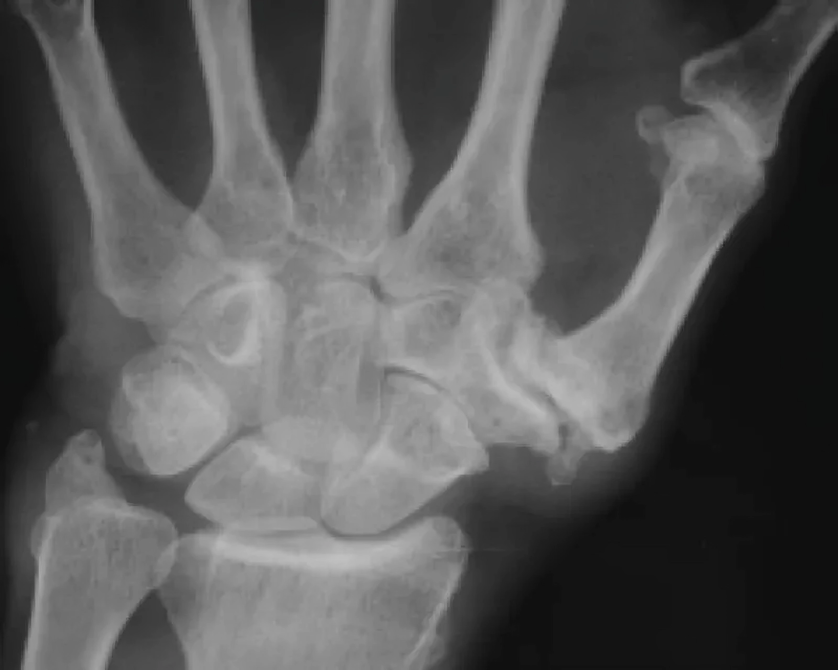

Thumb Base Arthritis

Arthritis affecting the base of the thumb is one of the most common painful conditions affecting the hand. This occurs when the smooth bearing surfaces of the joint become worn resulting in bone rubbing on bone, this causes pain and stiffness in the thumb and can result in difficulties doing buttons, opening jars and many other activities as well as deformity of the thumb.